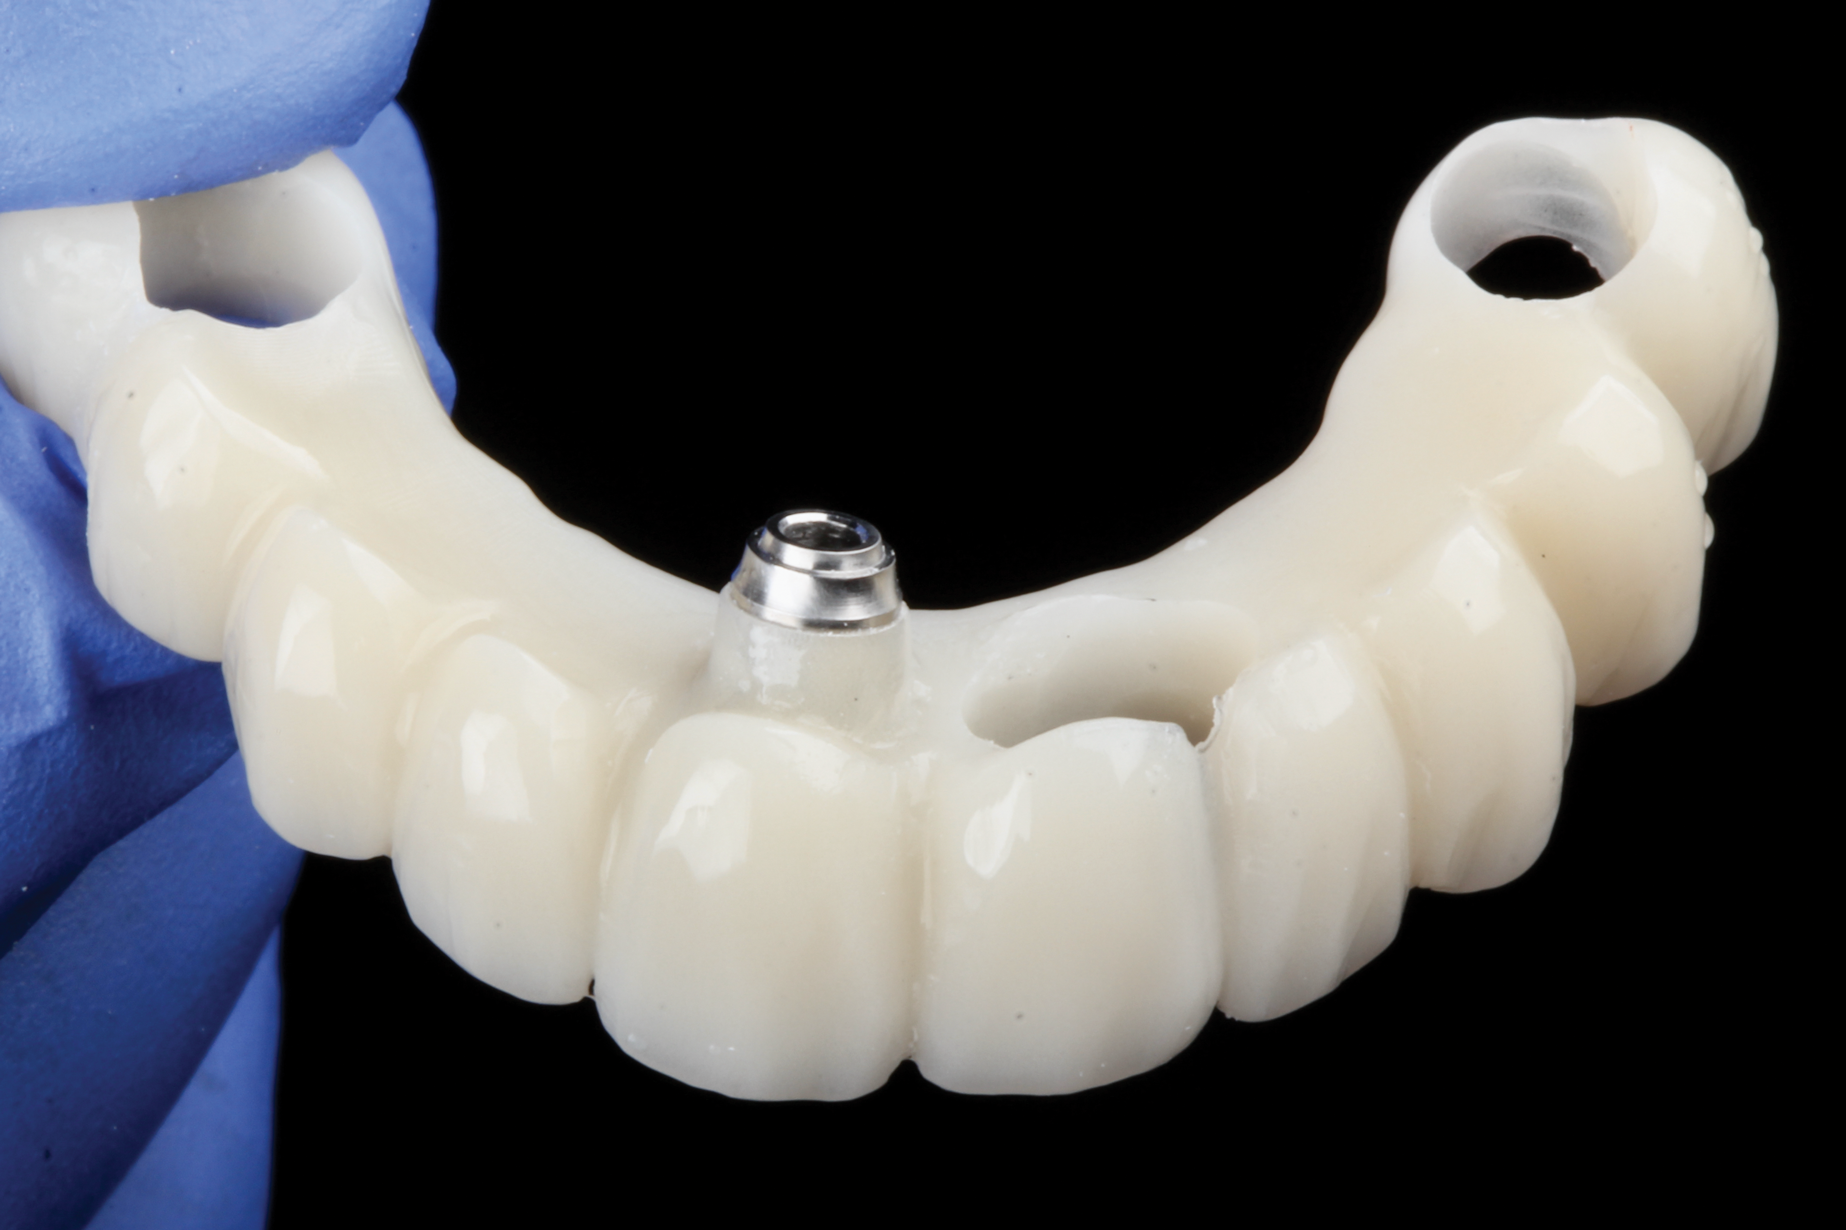

Predictability governed every aspect of this plan. Prior to the surgical phase of treatment, the clinical team scrutinized their bank of statistical analysis from 40 previously treated patients indicating coronal, apical, and angular deviations using robotic guidance. Each consideration of tissue augmentation, bone remodeling, implant placement, and prosthesis adjustment creat-

ed "confidence intervals" for the success of this case. Knowing the predictability of the technology, the surgeon could proceed to extract the necessary teeth and place the four implants. The provisional was already prepared with one of the anterior abutments embedded to facilitate alignment with the remaining implants (Figure 11). The patient eventually was restored in both the maxilla and mandible, with four implants in each arch to create an esthetic smile and functional restoration that was anticipated to be long-lasting (Figure 12).

Fig 11. Provisional prepared with an anterior abutment to facilitate implant alignment.

Figure 11